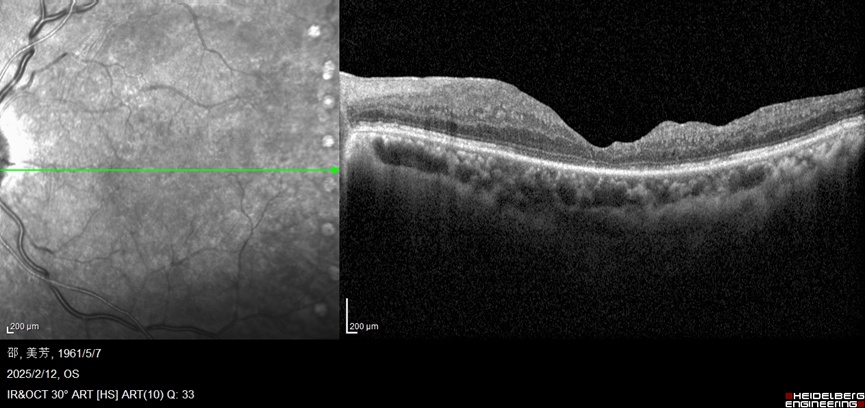

病例夹 邵阿姨(化名)因糖尿病视网膜病变曾在外院接受全视网膜光凝治疗,后因黄斑水肿在2024年一年内接受7次眼内抗VEGF药物注射。然而今年1月,她的视力再次下降,听闻奉城医院眼科有上海眼病防治中心的专家坐诊,便慕名而来。 经过专家陆士恒主任详细检查,发现其目前眼底病情为“黄斑水肿合并黄斑前膜”。 “黄斑前膜就像一层‘疤痕膜’,拉扯黄斑区导致水肿反复,单纯抗VEGF治疗难以根治。”陆主任向邵阿姨解释道。经团队深入讨论,决定为邵阿姨实施“玻璃体切割术+黄斑前膜剥除术+地塞米松缓释剂植入”联合手术,精准解决多重病理问题。 术后三个月,邵阿姨黄斑水肿完全消退且未复发,视力较术前显著提升,生活质量明显改善。 技术创新 三管齐下,破解治疗难题 微创玻璃体切割术: 彻底清除玻璃体腔异常牵拉,为后续操作创造清晰视野; 黄斑前膜精细剥除: 在高倍显微镜下剥离增生膜,解除黄斑机械性牵拉; 地塞米松缓释剂植入: 长效抑制炎症反应,持续缓解水肿复发风险。 邵阿姨这次手术的成功开展,也标志着奉城医院眼科在复杂眼底病综合治疗领域迈上新台阶。 专家介绍 Introduce 陆士恒 主任医师 上海市眼病防治中心 专家门诊 每周三上午 特长: 上海市眼病防治中心知名专家,具有丰富的白内障、眼底病诊断治疗经验,擅长玻璃体视网膜手术,如视网膜脱离、糖尿病性玻璃体视网膜病变、黄斑前膜等眼底疾病的微创手术;疑难复杂白内障的手术、白内障合并眼底病的联合手术;各种泪道疾病治疗。 专家提醒 糖尿病患者应每年至少进行一次眼底检查,若出现视物变形、眼前黑影、视力骤降等症状需立即就诊。对于顽固性黄斑水肿合并前膜的患者,及时手术干预是挽救视力的关键。 奉城医院眼科 守护光明,我们始终在精进 奉城医院眼科秉承“精准、微创、长效”的治疗理念,持续引进国际前沿技术,致力于为复杂眼底病患者提供更优质的治疗方案。如果您或家人正受眼底疾病困扰,欢迎去奉城医院眼科门诊咨询。 奉城医院眼科就诊信息 Ophthalmology Consultation Information 门诊时间: 全年无休, 8:00-11:30, 13:00-16:30 咨询电话:021-57522565-8140 地址:奉贤区川南奉公路9983号1号楼4楼